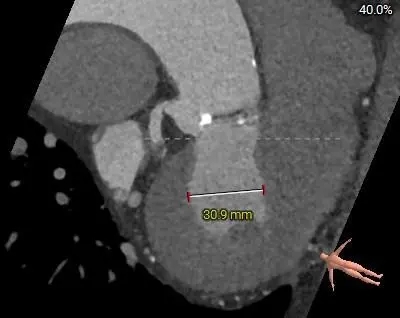

主动脉根部测量

周长径23.8

周长径27.1

L:32.9 N:33.3 R:27

周长径25.3

周长径31

瓣膜轻微增厚

无钙化

-

三叶瓣纯反流

瓣环23.8

瓣叶轻微增厚、无钙化

流出道27.1mm,敞口型

瓣上结构测量

周长径23.3

周长径23.4

周长径23.78

周长径23.9

周长径24

周长径24.4

瓣叶轻微增厚,瓣上多平面可参与锚定

冠脉风险评估

LCA Height 14.1mm

RCA Height 16.3mm

LCA & Leaflet 14.9mm&11.6mm

RCA & Leaflet 13.7mm&12.7mm

瓣环水平夹角49度,非横位心

冠脉高度可,瓣叶不长,冠脉阻挡风险不高

外周入路评估

降主动脉可见折角

腹主动脉、主动脉弓可见钙化瓣口

主动脉弓走行平缓

球囊扩张策略:不预扩

瓣膜型号:ScienCrown TAVTF27mm(oversize13.4%)

入路选择:右侧股动脉主入路,超硬导丝支撑下植入大鞘